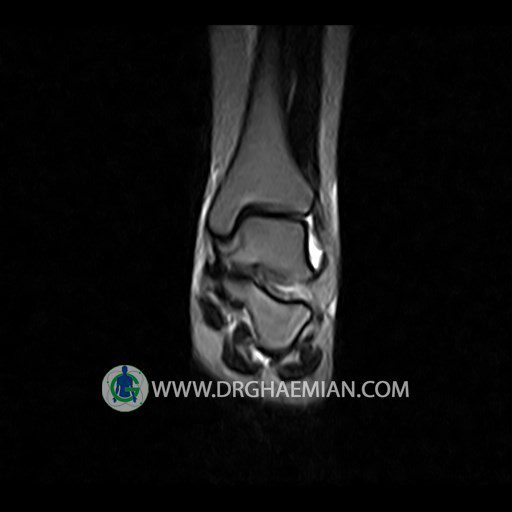

پزشکان اغلب از تصویربرداری ام آر آی برای تشخیص و درمان عارضه های پزشکی که فقط با استفاده از اشعه ایکس یا میدان مغناطیسی و امواج رادیویی قابل مشاهده است، استفاده می کنند. دستگاه ام آر آی تصاویر دقیق از ساختار های داخلی بدن ایجاد می کند. در این کیس تورم مچ پا بیمار مشاهده می شود.

Technique: Sagittal T1, T2 , Axial GE , coronal & sagital fatsat .

– Mild soft tissue swelling around the knee

is seen